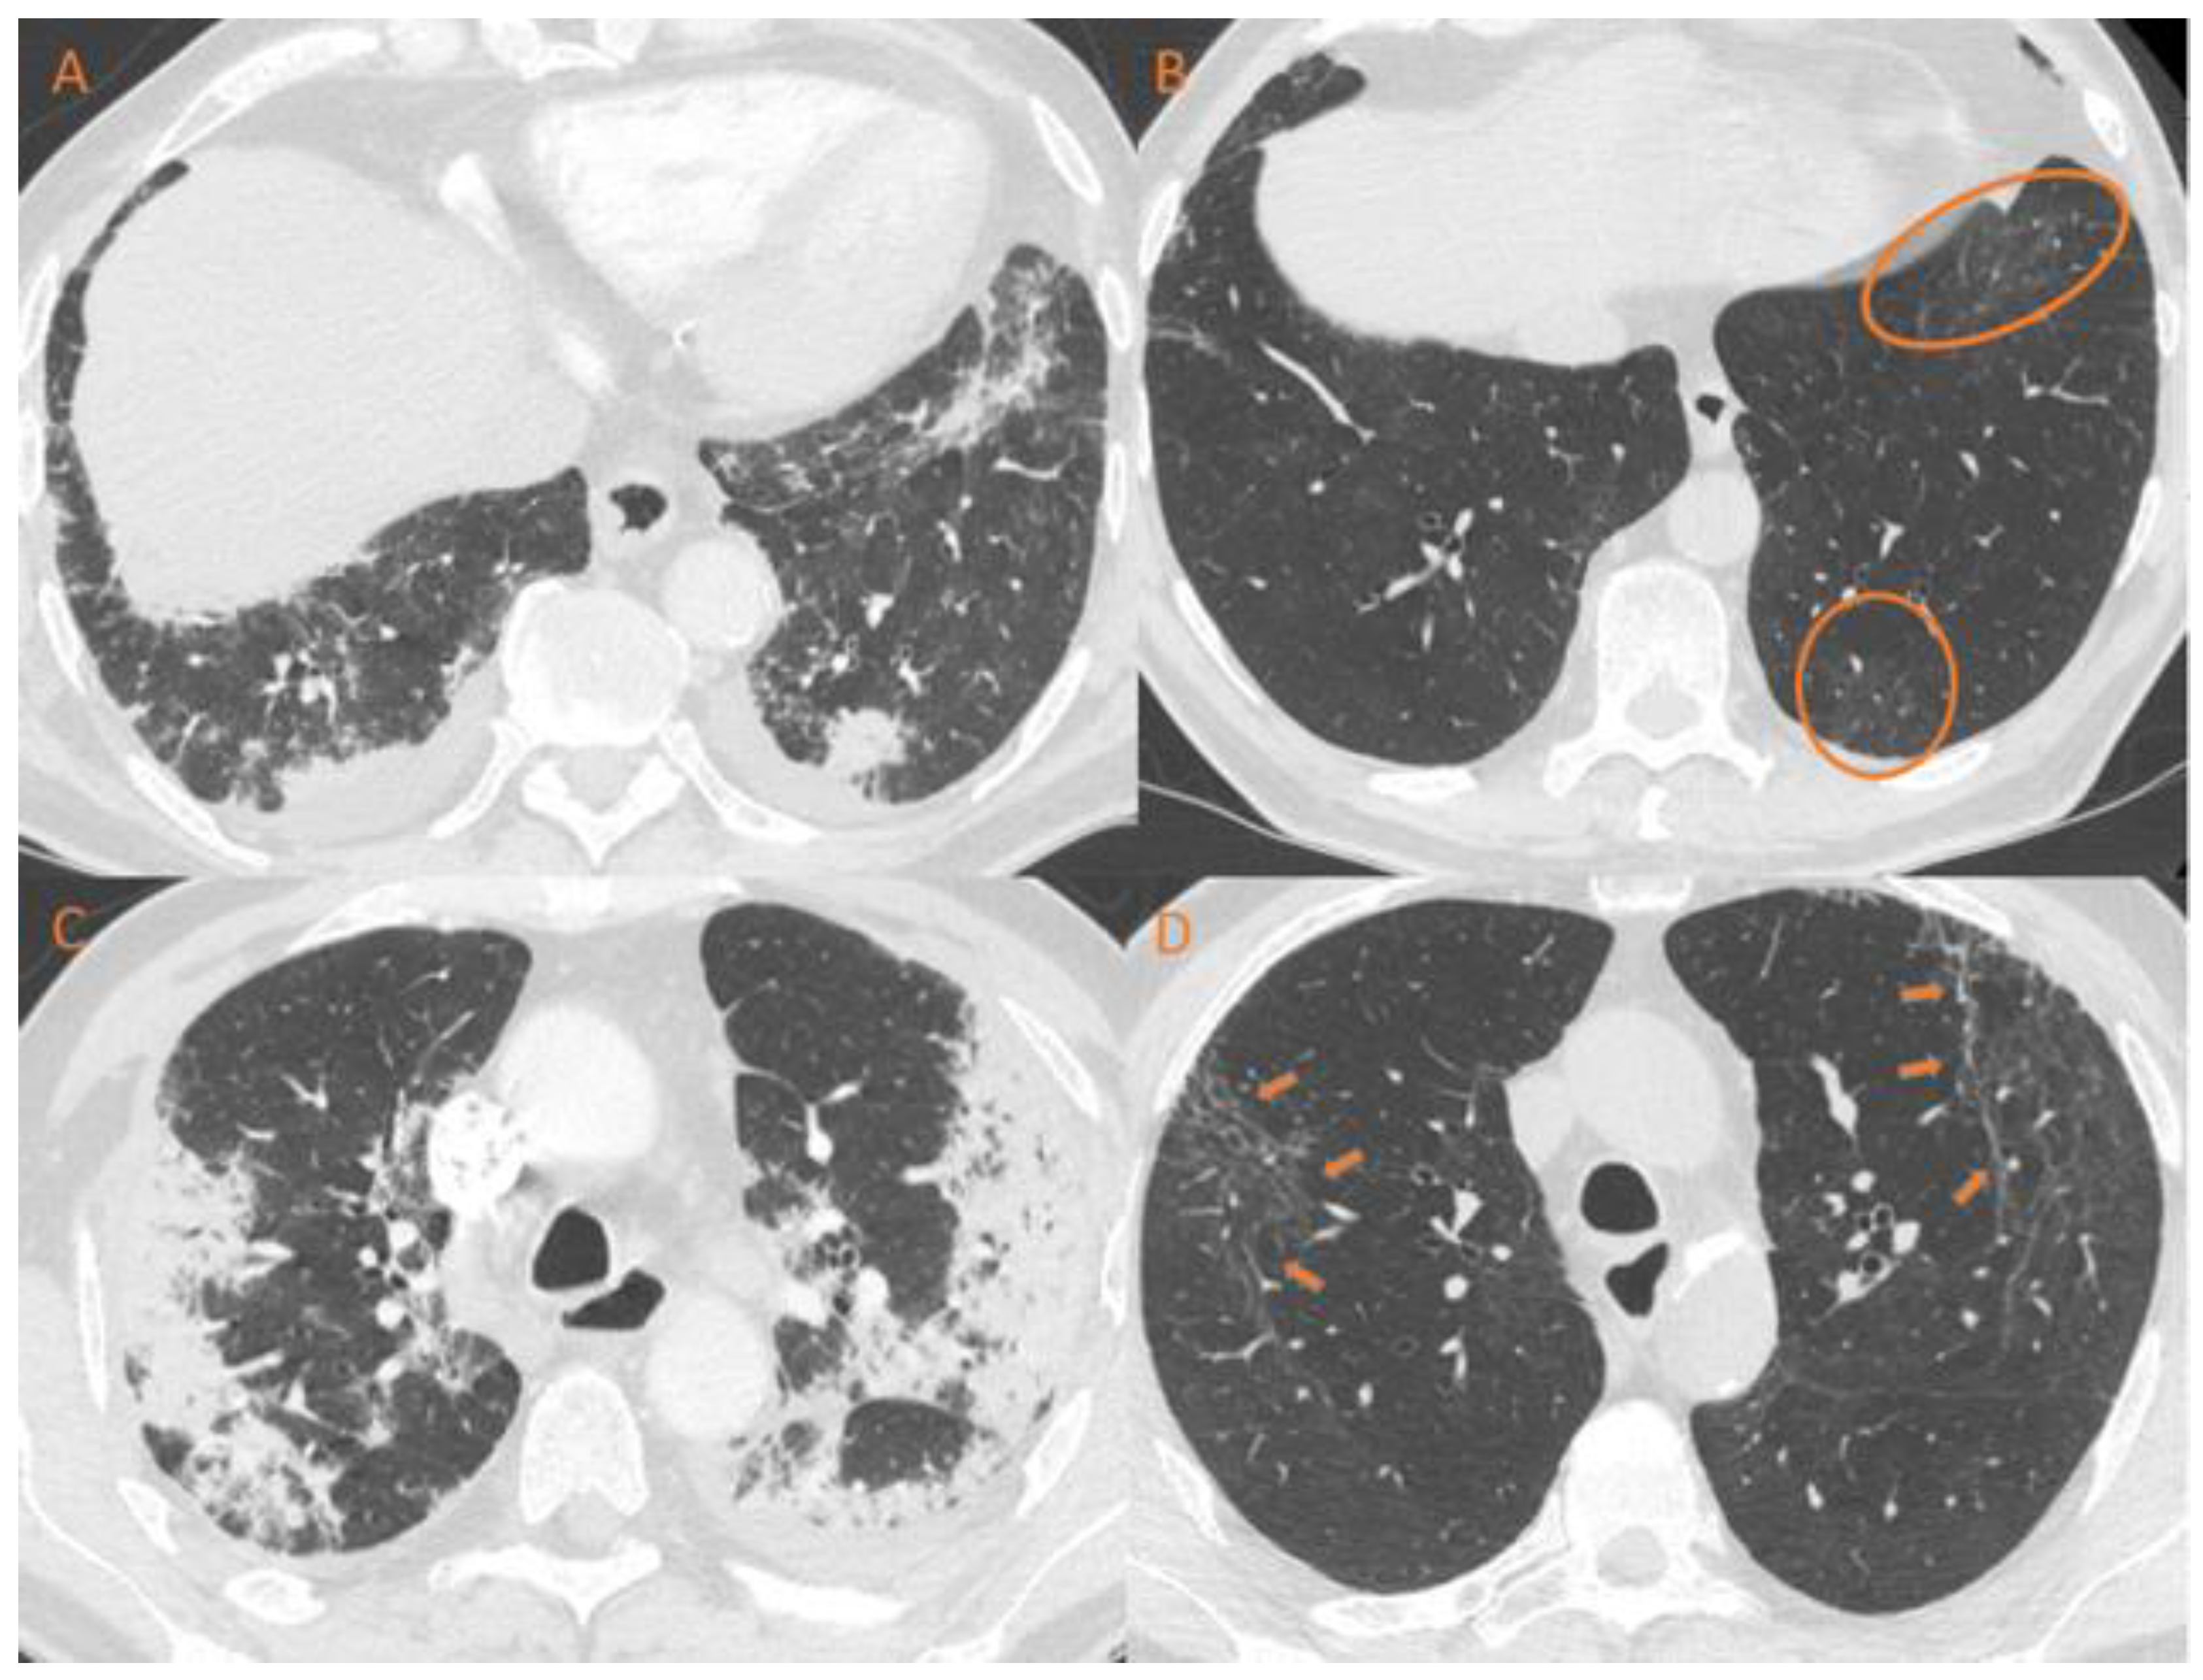

3.1. Respiratory Assessment